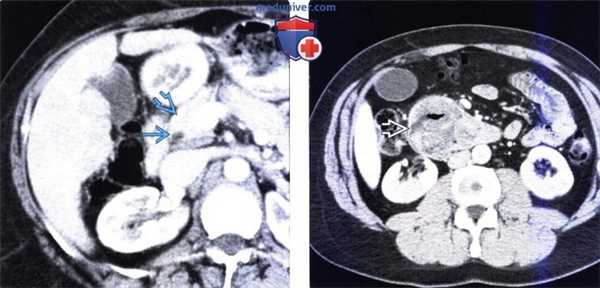

(Слева) На аксиальной КТ с контрастным усилением у этого же пациента определяется, что головка поджелудочной железы не изменена, в то время как общий желчный проток: в дистальных отделах остается расширенным.

(Справа) На аксиальной КТ с контрастом у этого же пациента определяется большое объемное образование в просвете второй и третьей части двенадцатиперстной кишки, которое обусловливает обструкцию протоков в области относительно низко расположенной Фатеровой ампулы. При эндоскопическом исследовании был подтвержден рак двенадцатиперстной кишки, развившийся в ворсинчатой аденоме.в) Дифференциальная диагностика рака двенадцатиперстной кишки: